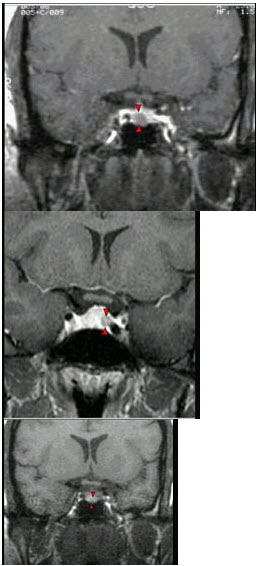

女,38岁,头痛、闭经,MRI检查如图,选择最可能的诊断( )

A:垂体囊肿

B:垂体梗死

C:转移瘤

D:垂体微腺瘤

E:垂体脓肿